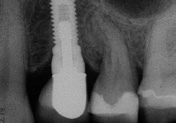

Aufgrund einer fortgeschrittenen parodontalen Erkrankung und eines schweren Knochenverlustes rund um den infizierten Zahn, musste der obere Prämolar des Patienten extrahiert werden. Im posterioren Oberkiefer wurde ein intraalveolärer Knochendefekt der Klasse I diagnostiziert, ohne eine Dehiszenz oder einen Fenestrationsdefekt vorzuweisen.

Dieser Patient wurde bereits im Jahr 1991 behandelt. Der Fall zeigt eine der ersten klinischen Anwendungen von Geistlich Bio-Oss Collagen. Aufgrund des intraalveolären Knochendefekts wurde eine Frühimplantation mit gleichzeitiger Augmentation durchgeführt. Die Implantation wurde 6 Wochen nach Extraktion des Prämolars vorgenommen. In der postoperativen Phase erfolgte eine unauffällige Weichgewebeheilung nach Extraktion. Für die Implantatinsertion wurde der Frühimplantationsansatz mit einer Heilungsphase von 6 Wochen gewählt. Die Knochenaugmentation wurde gleichzeitig mit der Implantatinsertion durchgeführt. Das Implantat wurde nach der Lappenpräparation an einer Stelle mit einem schweren Knochendefekt eingesetzt.

Für den Knochenaufbau wurde Geistlich Bio-Oss Collagen in den Defekt appliziert und nach der Augmentation die Eingriffsstelle mit einem Kollagenvlies abgedeckt. Weitere 6 Monate nach dem Eingriff wurde die endgültige Kronenrestauration eingesetzt. Bei der weiteren Nachuntersuchung nach nunmehr 25 Jahren zeigte die Röntgenaufnahme ein stabiles Implantatlager und das klinische Bild bei der Nachkontrolle einen ästhetischen Zahnstatus.